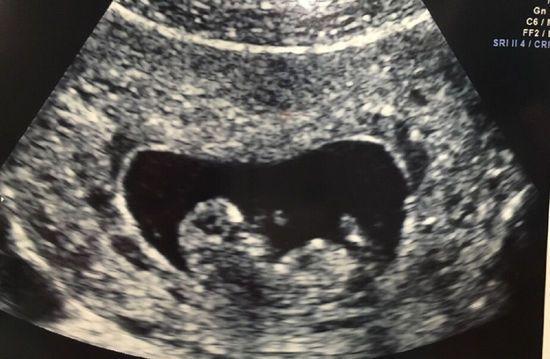

不同器官的b超检查有其重点观察内容,心脏超声需测量心腔大小、室壁厚度、瓣膜活动及血流情况,评估心脏功能;产科超声中,早孕重点观察孕囊、胎芽、胎心,中晚孕则需系统筛查胎儿结构(如头围、腹围、股骨长度,以及唇裂、心脏畸形等);甲状腺检查则关注结节的大小、形态、边界、内部回声及钙化情况,TI-RADS分级是评估甲状腺结节良恶性的常用标准,b超还可引导穿刺活检、囊肿抽液硬化等介入操作,实时显示针尖位置,提高操作安全性。